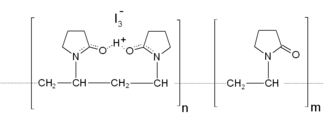

Повидон-йод, повидон-йодин (лат. Povidonum-iodum, англ. Povidone-iodine) — лекарственное средство, антисептик для местного применения. По химическому составу представляет собой комплексное соединение йода с поливинилпирролидоном (ПВП). Концентрация активного йода в комплексе 0,1—1 %. Оказывает антисептическое, дезинфицирующее, бактерицидное, противогрибковое, противопротозойное и противовирусное действие.[1] Не имеет резистентности (привыкания).

Повидон-йод представляет собой комплекс повидона (поливинилпирролидона), иодоводорода и иода[7]